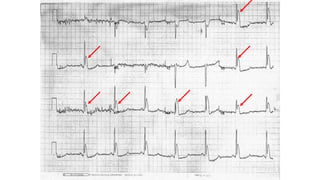

•Effects on cardiovascular system

•Osborne waves

Effects on immunesystem •Immunosupression •Effects on cardiovascular system •Bradyarrythmias •Hypertension( due to peripheral vasoconstriction) •Hypotension (due to negative inotropic effect) •Osborne waves